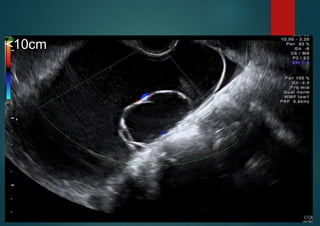

<10 cm

Serous cystadenoma

unilocular, regular walls, <10 cm